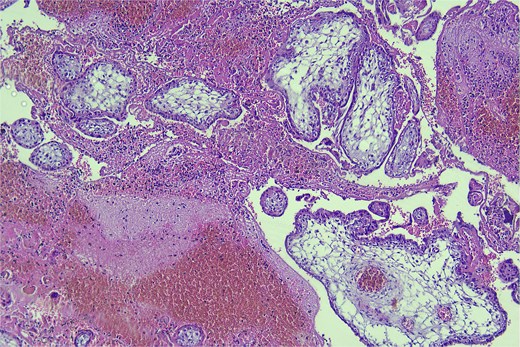

Histopathology on day six confirmed the diagnosis of RPEP, with the presence of blood, fibrin, and chorionic villi (Fig. 6).

Hematoxylin and eosin stain, high-power magnification (400×) of the surgical material, demonstrating blood, fibrin, and chorionic villi.